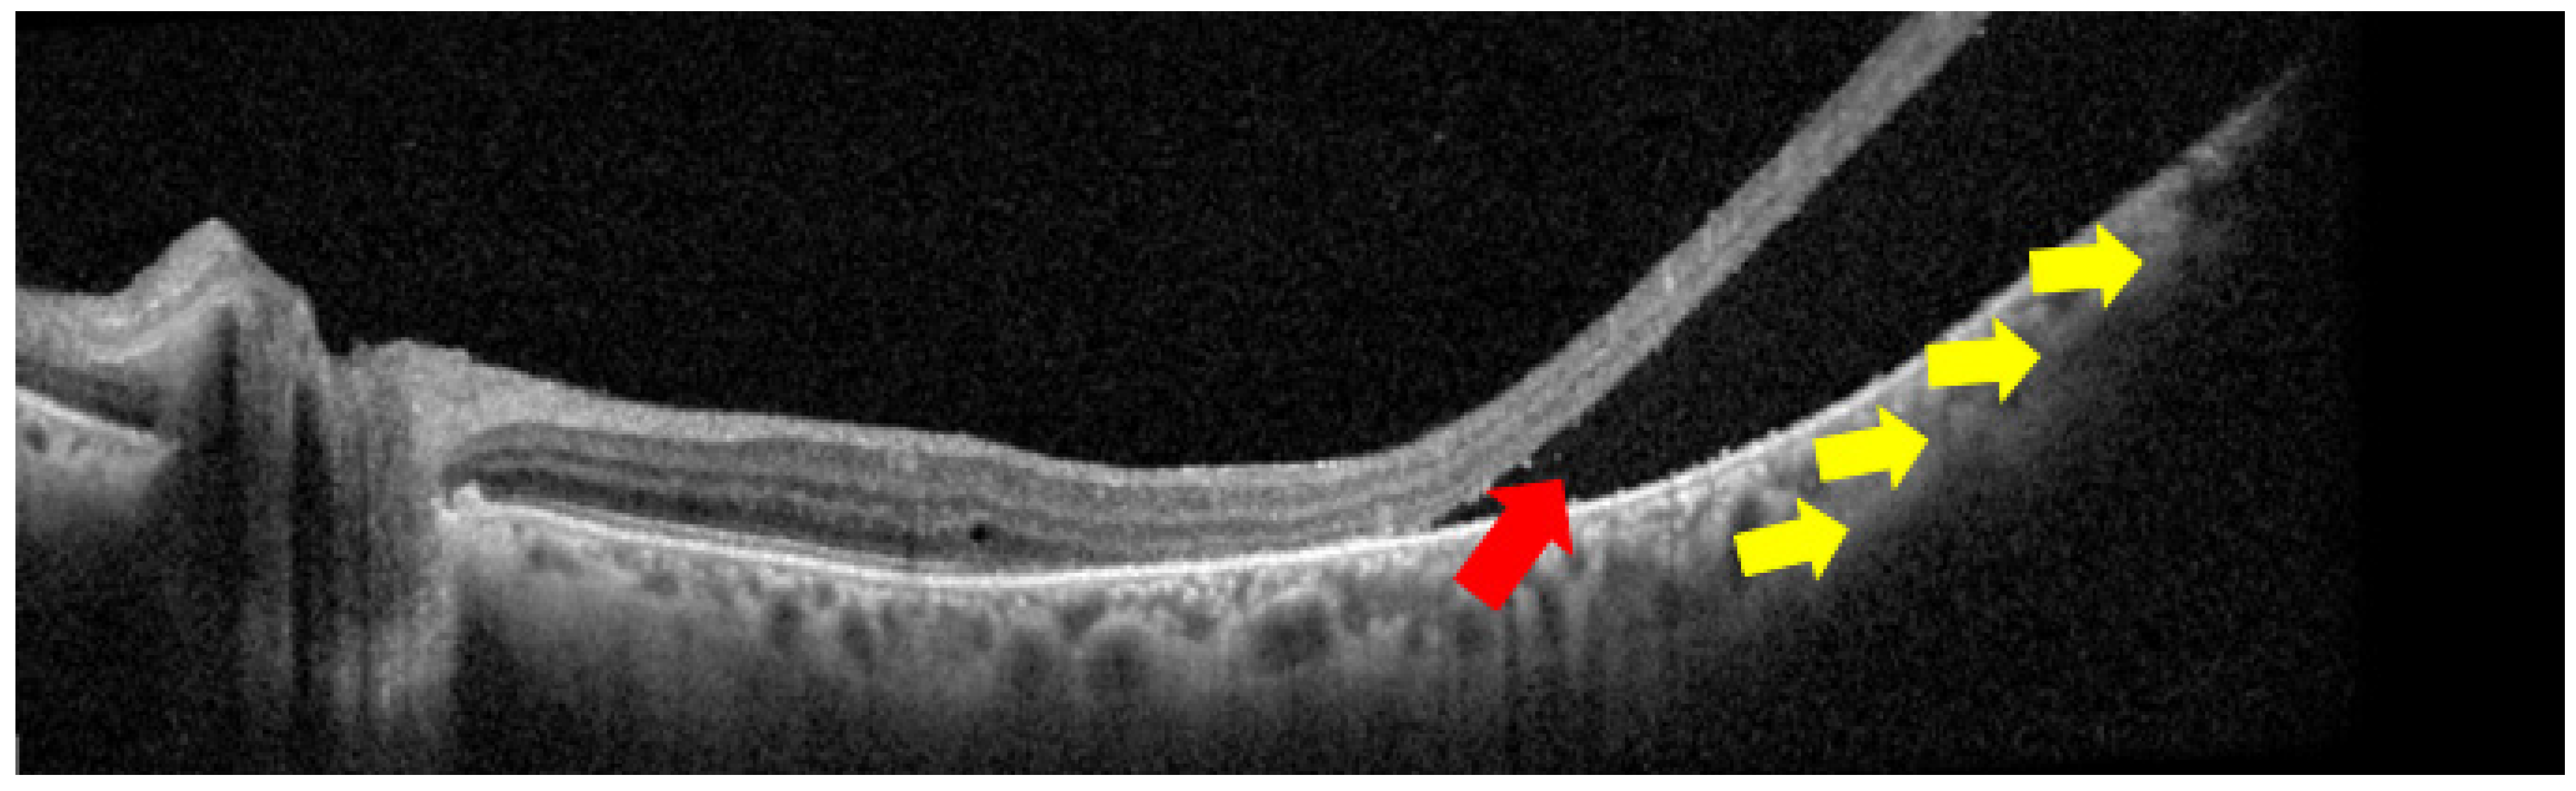

- Guner, M.K.; Ferenchak, K.; Olsen, T.W.; Dalvin, L.A. Optical coherence tomography findings in choroidal melanoma-associated subretinal fluid. Retina 2022, 42, 2159–2168. [Google Scholar] [CrossRef]

| Bacillary layer detachment (BALAD) | Structural OCT through lesion apex | Presence → exudative activity; larger tumors | Disease activity marker | Güner et al., retrospective melanoma cohorts: BALAD associated with tumor-related SRF and exudation; prospective UM validation still needed [44]. |